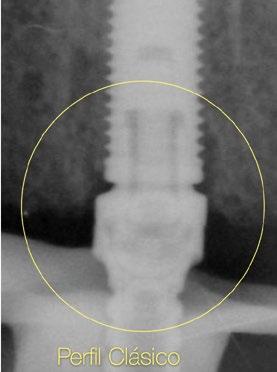

tura de la encía y calcular la angulación del implante con respecto a la emergencia de los dientes para determinar la necesidad de utilizar un pilar angulado. Con la evolución de la implantología, los conceptos de planificación protésicamente guiada, las filosofías de “cero pérdida ósea” (zero bone loss concepts, Linkevicius [Ref.1]) y los conocimientos de la estética actual sobre implantes están presentes a la hora de colocar los implantes y rehabilitarlos. El objetivo ya no es buscar una rehabilitación funcional, sino que también es lograr una apariencia estética natural duradera y estable a lo largo del tiempo evitando problemas como la recesión gingival o la pérdida ósea marginal e interproximal. El nivel de conocimiento que existe en implantología unitaria implica tal cantidad de conceptos y detalles a nivel biológico y protésico que dificulta mucho y hace prácticamente imposible la utilización de los pilares Multi-unit clásicos para situarlos en la zona transgingival y lograr emergencias estéticas adecuadas. Como siempre, Nobel Biocare ha comprendido estas necesidades y se ha adaptado a estos requisitos introduciendo nuevos diseños de perfiles que se adaptan mucho mejor a este tipo de situaciones y resultados. El objetivo de esta publicación es presentar las características de los nuevos pilares Multi-unit y sus finalidades, así como también las indicaciones de su utilización.

cuenta que el volumen del pilar va a ocupar prácticamente toda el área de la altura de tejido supracrestal (“Suprecrestal tissue height” Ref. 11) y debe estar “camuflado” en dicha zona de transición ocupando gran parte del espacio para el tejido conectivo supracrestal y del perfil de emergencia de la restauración (Ref. 13). Ya sea un pilar recto o angulado, debido a sus formas robustas y perfiles anchos, resulta difícil de planificar su colocación en zonas estéticas ya que el complejo implante-pilar se va a comportar como un implante tipo “tissue level” (Ref.14)

(Fig.1). Con los diseños clásicos de pilares no se van a poder respetar las concavidades subgingivales deseadas y siempre va a implicar la eliminación de hueso, sobre todo a nivel interproximal y vestibular en la zona del cenit del diente (Ref.15) (Fig.2). Las consecuencias automáticas serán picos de hueso interproximales reducidos, papilas más cortas y dientes con cenits más planos y anchos en el tercio gingival. Incluso en situaciones de implantes adyacentes puede provocar la pérdida o ausencia total de papila interimplantaria (Ref.7) (Fig.3).

Innovaciones y características del nuevo pilar Multi-unit: perfiles para preservar Debido a esta compleja situación, se ha desarrollado una nueva línea de pilares Multi-unit que rompe con los diseños clásicos y que se presenta a continuación: (Figs. 4,5).

Con respecto al Multi-unit recto, su principal característica es la emergencia desde la plataforma del implante con un perfil completamente cóncavo. Por una parte, va a maximizar el efecto de “cambio de plataforma” en su parte más crestal a nivel de la plataforma del implante y por otra va a facilitar mucho más espacio para la creación de tejido conectivo supracrestal a lo largo de toda la transición hasta la plataforma restauradora. El perfil cóncavo del pilar también respetará en mayor medida los espacios comprendidos entre el pilar y el hueso interproximal (en el caso de una colocación subcrestal entre 1,5 y 2mm) para poder preservar al máximo las estructuras anatómicas presentes que soportarán las papilas periimplantarias.

Así como el diseño clásico de pilar hacía prácticamente imposible la colocación de implantes inmediatos en zona estética, el nuevo perfil cóncavo del pilar Multi-unit hace que se convierta en un pilar ideal para estas situaciones. La altura de pilar de 3 ,5 mm, hace que se pueda colocar la plataforma del implante en la posición corono-apical deseada con respecto al margen gingival sin involucrar el hueso adyacente y permitiendo desarrollar un mínimo perfil de emergencia restaurador más horizontal para soportar cenit y tejido interproximal. (Fig.6-7) Otra característica de diseño importante es la reducción del bisel de la plataforma res-

tauradora tanto en los pilares rectos como en los pilares angulados. Sin cambiar su diámetro clásico de 4,8mm ni su compatibilidad para atornillar y asentar cualquier aditamento restaurador de toda la gama Multi-unit, el nuevo pilar presenta una plataforma mucho más fina y estilizada que facilitará también su inserción incluso sin necesidad de utilizar la fresa “bone mill” o molinillo de hueso. De esta manera no solo se seguirá incrementando la preservación ósea, sino que también se reducirán los tiempos quirúrgicos al evitar tener que atornillar y desatornillar la guía del molinillo o “Bone Mill Guide”. (Figs. 8-12)

Sin duda, los perfiles mejorados del Multi-unit recto aportan beneficios claros e inmediatos que facilitarán la práctica clínica, pero el pilar que realmente revoluciona e innova es el nuevo pilar angulado. (Fig.13)

En esta ocasión se ha logrado reducir el tamaño del robusto pilar original a la mínima expresión, obteniendo líneas suaves, finas y redondas. De nuevo, esta forma comulga mucho más con los conceptos mencionados anteriormente. Además, proporcionará un verdadero impacto en la manera de planificar y en los resultados a largo plazo. Seguidamente se describen algunos ejemplos clínicos para las angulaciones de 30º y 17º respectivamente: